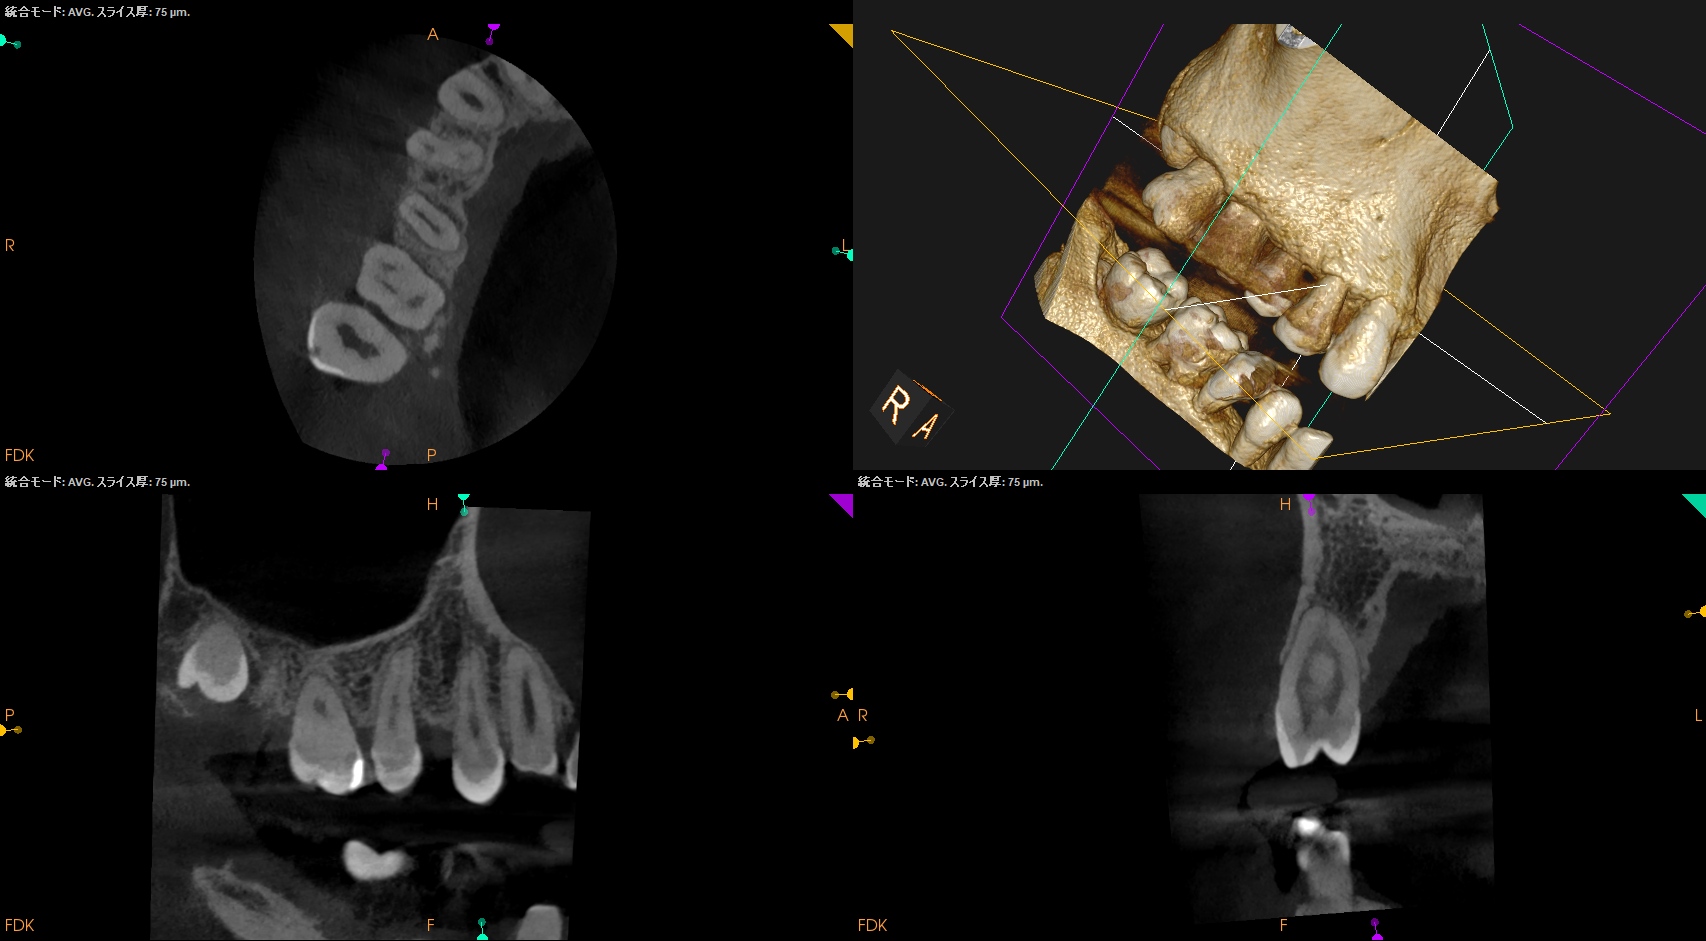

PA, CBCTも撮影した。

#14

MB

DB

P

#14と同じような症状がある#2,5であるが、

#2

#5

B

無傷の#5にも同じような症状がある。

ということは…

#14の咬合痛?のようなものは病気でなく、そう感じるという臨床的状態で, それだからといって治療を要するものではないだろう

ということがわかる。

初診時と比較した。

問題が劇的に解決していることがわかる。